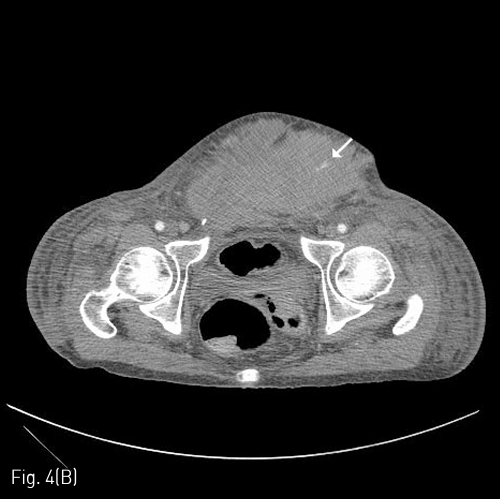

Fig 7B

(B) A skin defect could be observed in the anterior abdominal wall in the abdominal CT taken on day 52 from the initial embolization therapy with all hematomas of the abdominal wall removed and no recurrent bleeding.